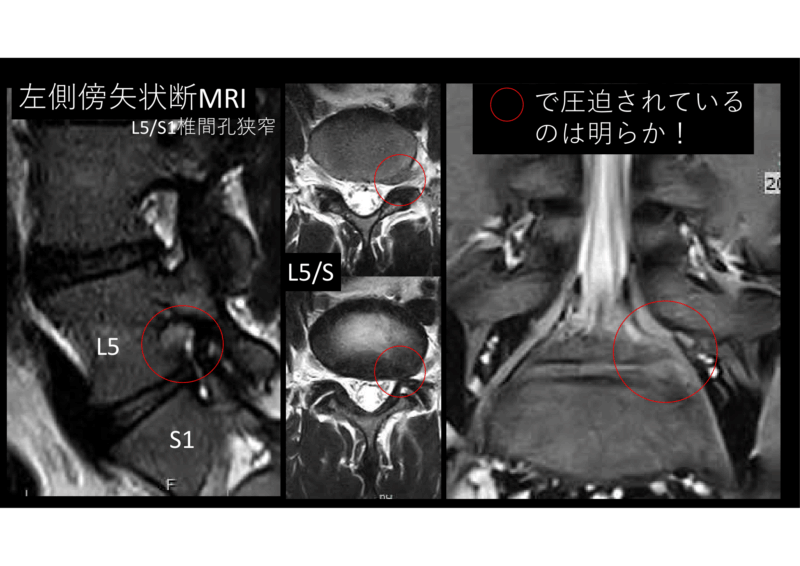

私の診断はL5/S1椎間孔狭窄+ヘルニア。

17歳で椎間孔狭窄もないだろう、と思われるかもしれません。しかし、右と比較して左には明らかに椎体からの骨棘がある。神経根は非常に狭い場所に押し込められています。

これに椎間板ヘルニア、とはいっても、有るか無いかの小さなものです。基本は狭窄です。初診で術式、手術日を決定し、19日後に手術となりました。